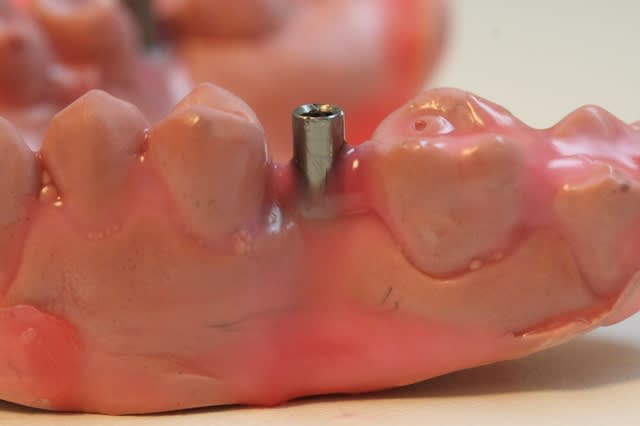

voyons maintenant un autre guide qui cette fois si utilise des canons de perçage en titane.

1 canon et empreinte

2 collage du canon avec du composite

3 attention à l'axe